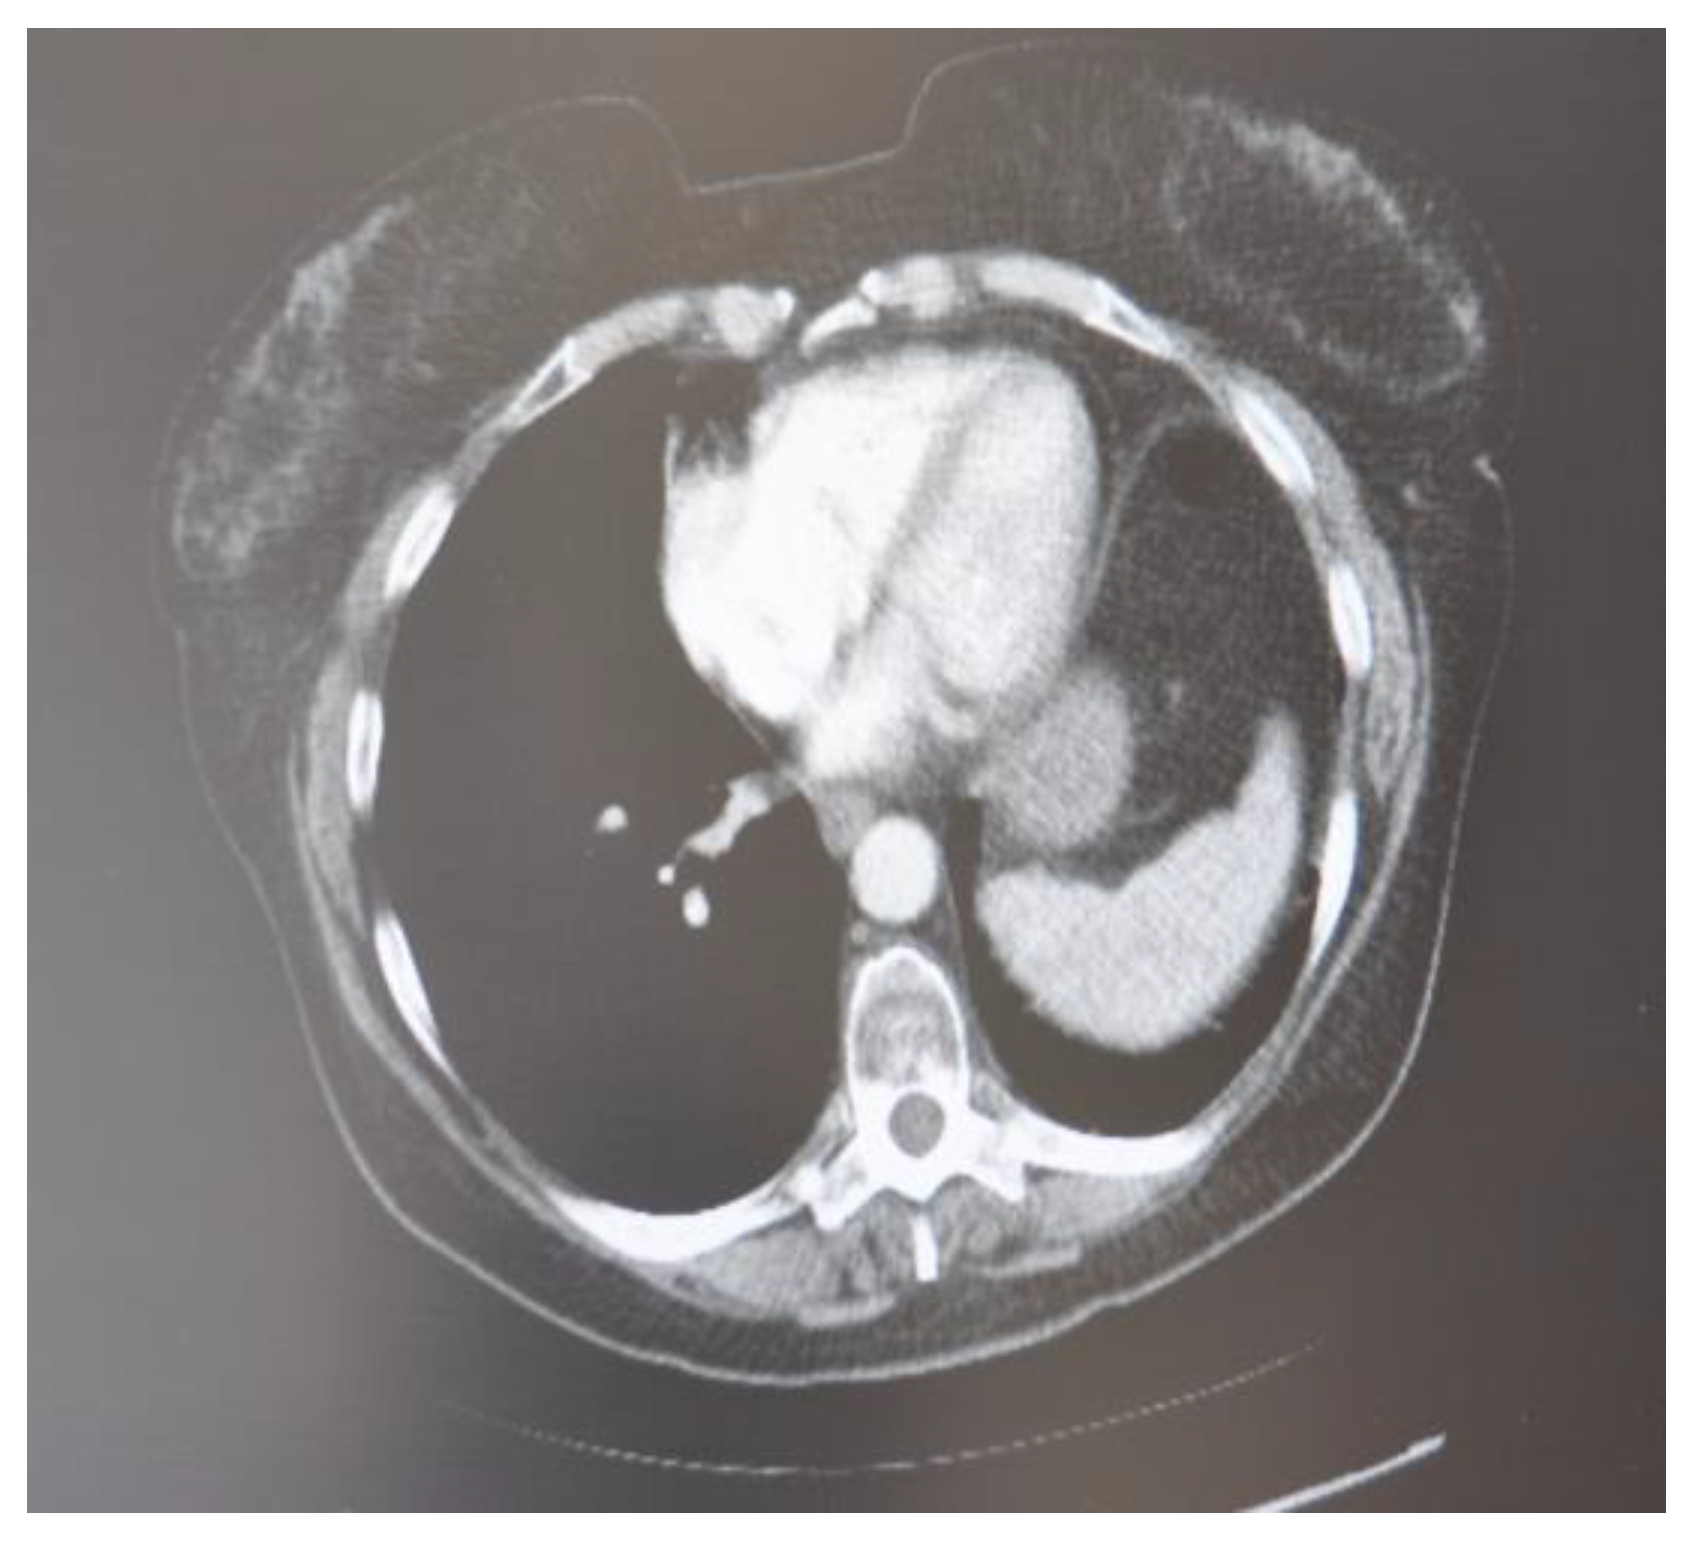

In March 2020, a 35-year-old patient arrived at our department with the results of a recently performed positive biopsy. For this reason, a CT scan of the chest, abdomen, and pelvis with means of contrast was performed in our department. CT examination confirmed the presence of several mediastinal lymph nodes. An anterior mediastinal lymph node with a diameter of (39 × 26 mm), a para-aortic lymph node with a diameter of (35 × 25 mm), a lymph node of the aorta-pulmonary window with a diameter of (30 × 20 mm) as well as several lymph nodes with diameters ranging from (27 × 16 mm) to (23 × 20 mm). Focal pleural thickening of 10 mm was confirmed at the posterior right lower lobe (peri-vertebral) (see Figure 1). For these reasons, it was decided to subject the patient to a cryosurgery intervention procedure as described above.

Figure 1. CT scan image executed.